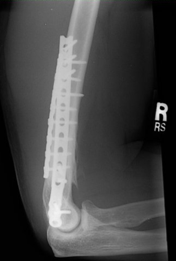

- x-ray.png (44.83 КБ) 9585 просмотров

Перелом голени. Обе кости. Стоит пластина. 7 лет назад. 1.5 года назад прошёл ВЛЭК. Всё официально. Сделали снимок. Хирург посмотрел. Посоветовался с председателем. Подписал - годен. 2 кат.